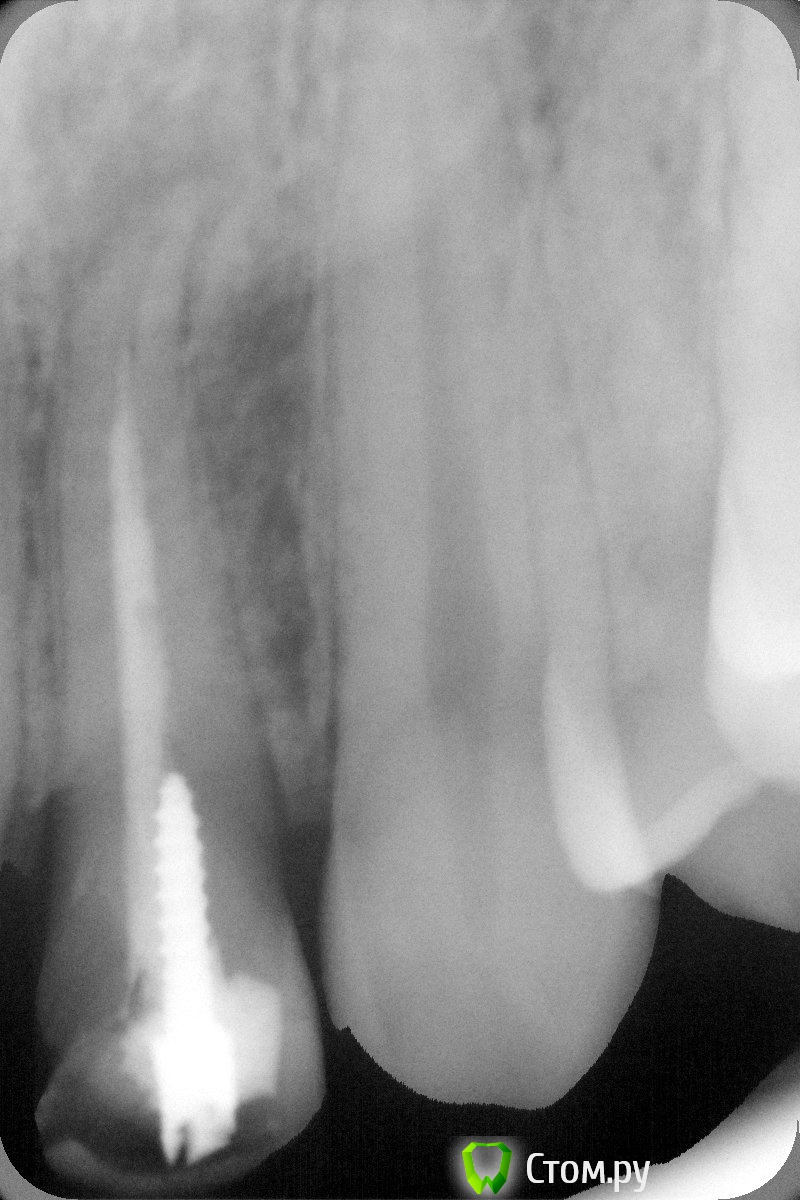

johniola Опубликовано 5 февраля, 2014 Поделиться Опубликовано 5 февраля, 2014 Девочка 19 лет из церковного приюта(иногда помогаю),22 зуб анкер+композит+хр периодонтитФото с свш +билд ап не нашёл,проостите Ссылка на комментарий